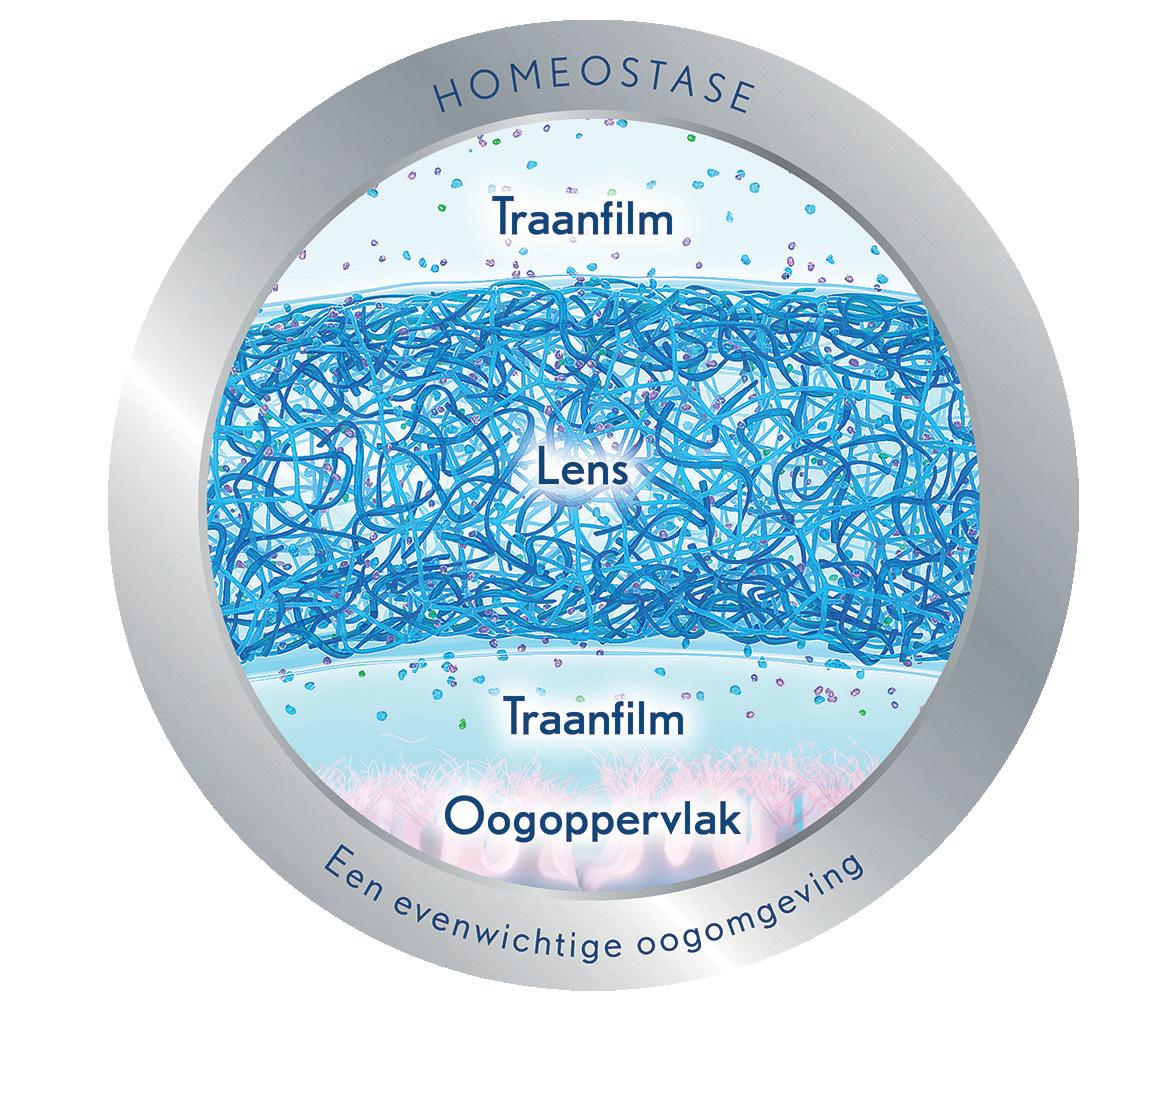

Droge ogen is daarom geen illusie, maar een serieuze aandoening die volgens Théa Pharma aandacht verdient. Branderige ogen, wisselend zicht, vermoeidheid en pijn zijn reëel, verdienen erkenning én een gerichte behandeling. Théa Pharma is ervan overtuigd dat effectieve zorg begint bij het serieus nemen van de klacht. Droge ogen is geen symptoom op zichzelf, maar het gevolg van onderliggende verstoringen in het traanfilmsysteem of in de aanmaak van de traan. Daarom verschuift de focus in de zorg steeds meer van louter symptoombestrijding naar bronbehandeling: het aanpakken van de oorzaak, niet alleen het verlichten van het gevoel.

Beide worden versterkt (of moeten we misschien zeggen: eerder opgemerkt?) door het toenemende gebruik van digitale apparaten1. In de praktijk kun je stellen dat het daarmee tijd is om te werken met oplossingen die niet alleen het zicht verbeteren, maar ook rekening houden met de stabiliteit van het oogoppervlak.

BELANG VAN VROEGTIJDIG HANDELEN BIJ PRESBYOPIE EN TRAANFILMPROBLEMEN

Bij zowel presbyopie als een verminderde traanfilmkwaliteit is het cruciaal om tijdig te starten met het aanbieden van passende oplossingen. Vaak beginnen de ongemakken subtiel: kleine klachten kunnen al langere tijd aanwezig zijn voordat iemand daadwerkelijk hulp zoekt. Dit betekent dat oogzorgprofessionals alert moeten zijn op vroege signalen, zodat ze de juiste vragen kunnen stellen en het gesprek over mogelijke oplossingen al kunnen openen voordat de klachten uitgroeien tot daadwerkelijke beperkingen.

Door proactief te handelen en patiënten vroegtijdig te informeren over beschikbare mogelijkheden, worden grotere problemen voorkomen en is de contactlensdrager minder geneigd om naar een andere kijkoplossing te zoeken. Het is daarom essentieel om niet te wachten tot de klachten significant worden, maar juist tijdig te handelen en de aanpassing richting een betere oplossing te starten.

Bausch + Lomb ULTRA® ONE DAY contactlenzen geven een unieke combinatie van comfort- en gezondheidsbevorderende stoffen af tijdens het dragen. Andere stoffen blijven behouden gedurende de 16 uur draagtijd om de traanfilm te beschermen, verrijken en stabiliseren2

2 Rah M. Ocular surface homeostasis and contact lens design. February 2021.

GERICHTE WERKING OP DE MUCINELAAG